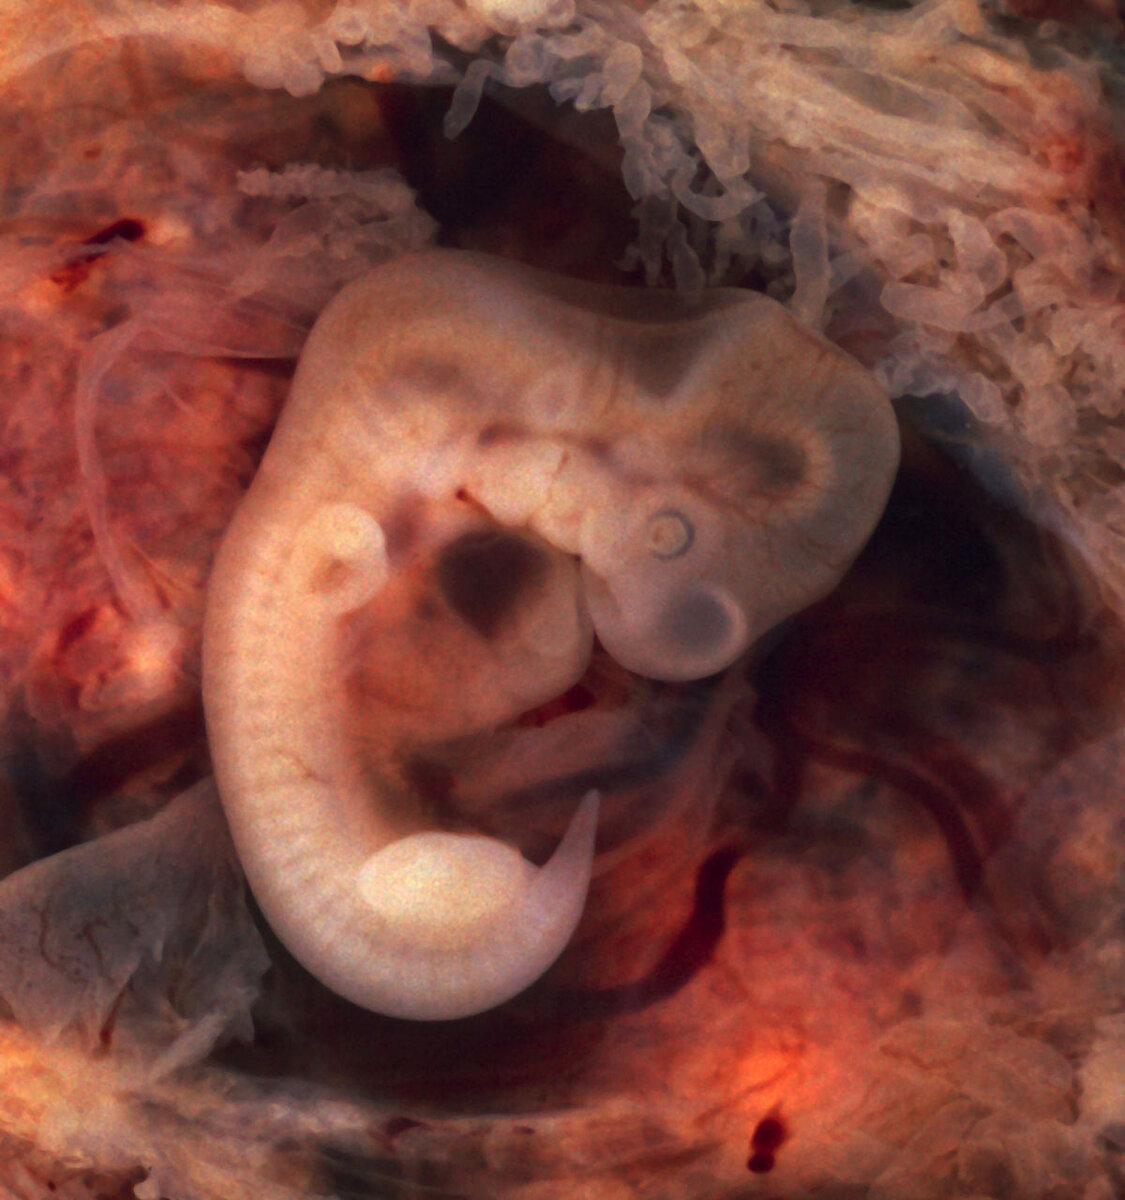

Эмбрион

К сожалению, даже после полного обследование и лечения пары, выявить причину удаётся не всегда. Но надо понимать, что даже отсутствие причины не исключает наступление успешной беременности!